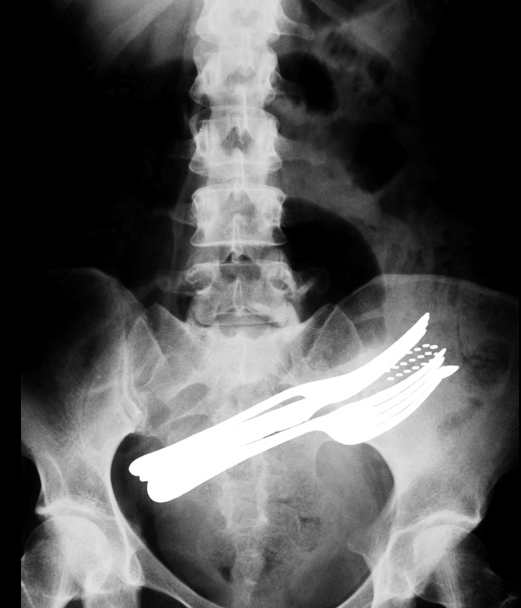

2) O esto que realmente es de otro mundo: la foto que ves abajo corresponde a una persona que se tragó dos tenedores, un lápiz de pasta y un cepillo de dientes.

Barcroft | The Telegraph